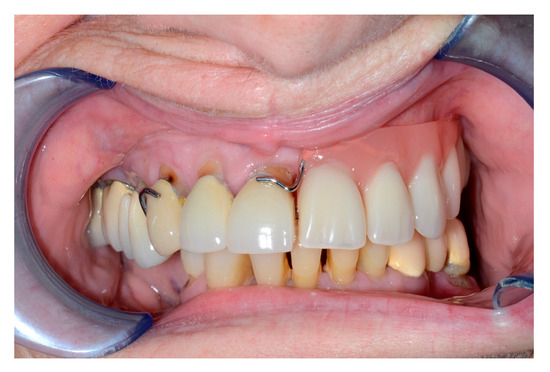

Here, support and volume are required to obtain an aesthetically pleasing and functional reconstruction. A DCIA with internal oblique muscle and skin in conjunction with an MFC (or a perforator flap) can satisfy the above requirements. The DCIA replaces the maxilla, while the MFC reconstructs the orbital walls, as seen in the patient below (Figure 1, Figure 2, Figure 3, Figure 4, Figure 5 and Figure 6).

Figure 5. Intraoral view with denture.